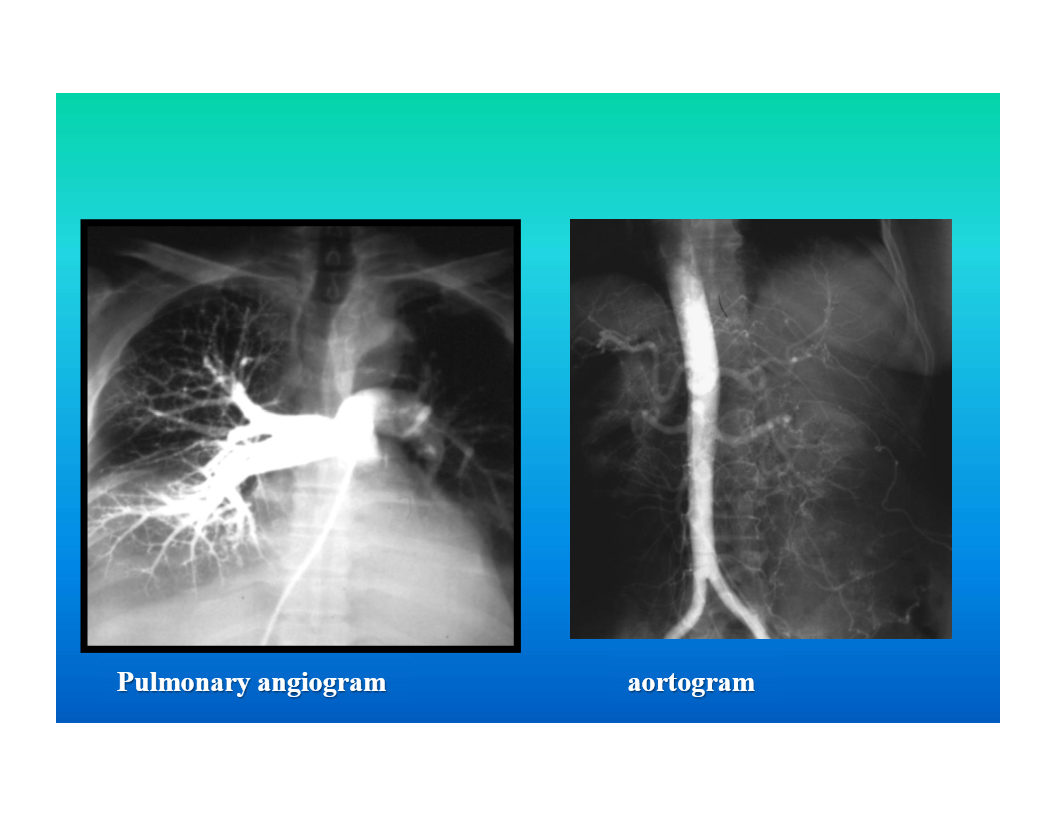

angiography

injection of a contrast agent into a blood vessel followed by xray imaging of the blood vessel or area of the body fed by that vessel

used to evaluate coronary arteries as well as peripheral vasculature

also used to evaluate abdominal vasculature

can be used in tumor evaluation and to guide treatment